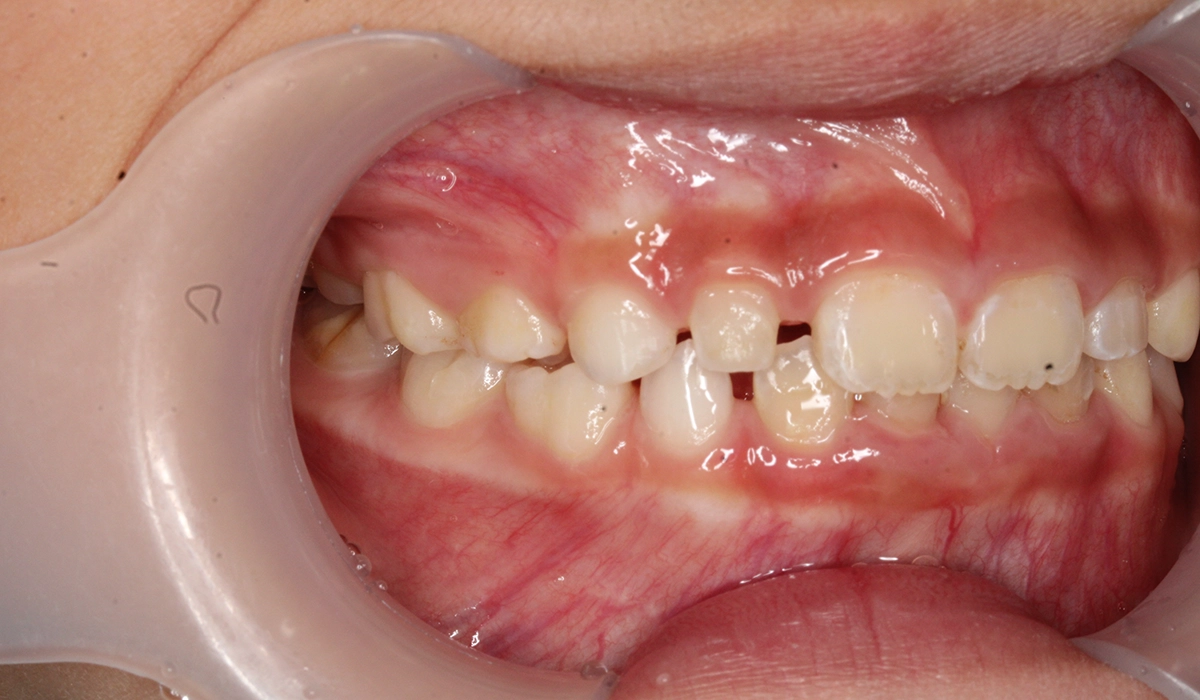

術前:左側

術後:左側